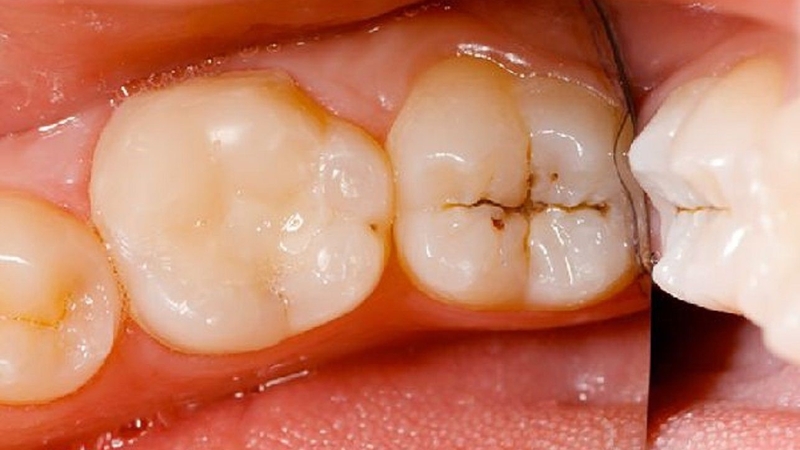

Răng sâu là hệ quả khi vi khuẩn, axit ăn mòn men và ngà răng, sau đó tấn công vào tủy răng. Sự hình thành sâu răng trải qua nhiều giai đoạn, bao gồm:

Sâu răng có thể gây ra nhiều vấn đề, một số biến chứng thường gặp bao gồm áp xe răng, sưng tấy hoặc sự hình thành mủ quanh răng bị sâu, cũng như tình trạng gãy hoặc hư hại răng ảnh hưởng đến khả năng nhai và sau khi mất răng có thể làm thay đổi vị trí của các răng lân cận. Khi sâu răng tiến triển nặng, người bệnh có thể phải chịu đựng cơn đau ảnh hưởng đến cuộc sống hàng ngày, dẫn đến sụt cân hoặc gặp khó khăn trong việc ăn uống.

Trong trường hợp răng chỉ sâu nhẹ, khi tổn thương chỉ ở phần men răng, bác sĩ thường tiến hành làm sạch và trám để khôi phục hoàn toàn. Nếu sâu răng đã ăn vào ngà mà không ảnh hưởng đến chân răng, có thể điều trị tủy và trám răng để bảo toàn khả năng ăn nhai.

Ngược lại, trong những trường hợp sâu răng gây viêm nặng, nhổ răng sâu có thể là giải pháp tối ưu. Sự phát triển của sâu răng có thể dẫn đến việc vi khuẩn tấn công vào chân răng và xương hàm. Bác sĩ có thể quyết định nhổ răng nếu tình trạng này nghiêm trọng, đặc biệt là khi chân răng bị tổn thương, có hiện tượng tụt lợi hoặc viêm nha chu.